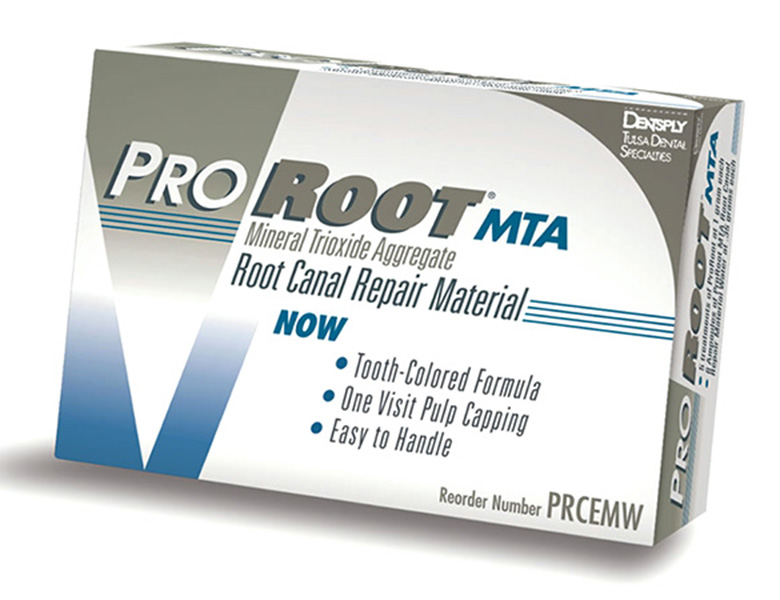

MTAセメント

高い殺菌性と封鎖性を持つの薬

治療の最後に根管を埋める、生体親和性の高い特殊なセメントです。

水分がある環境でも固まり、強い殺菌作用を長期間維持します。

根の先に穴が開いてしまったケースや、神経を保護する処置(覆髄)においても高い成功率を誇る、現代の根管治療に欠かせない薬剤です。